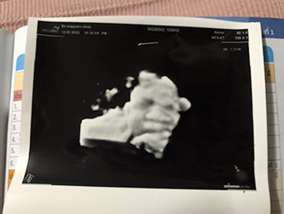

ขอดูภาพอัลตร้าซาวด์ของแม่ๆที่ได้ลูกชายหน่อยค่ะ หมอบอกว่าได้ลูกชาย เลยอยากเห็นภาพของลูกชายแม่ๆบ้าง

ลูกชายค่ะ #ทีมกันยา

ลูกชายค่ะอ้าขาเลย

จู๋ออกเด่นมากค่ะ